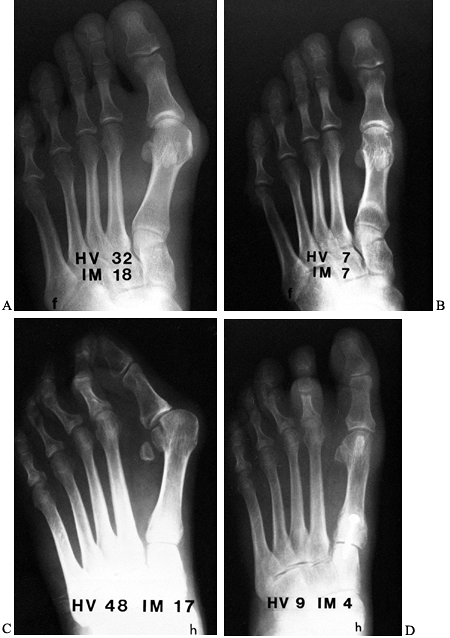

![]() |

|

Figure 112.13. Preoperative (A) and postoperative (B)

radiographs demonstrating satisfactory correction of a moderate hallux valgus deformity using a distal soft-tissue procedure and proximal osteotomy. Notice satisfactory realignment of the sesamoids and minimal shortening of the first metatarsal. Preoperative (C) and postoperative (D) radiographs demonstrating satisfactory correction of a severe hallux valgus deformity using the distal soft-tissue procedure and proximal crescentic osteotomy. |